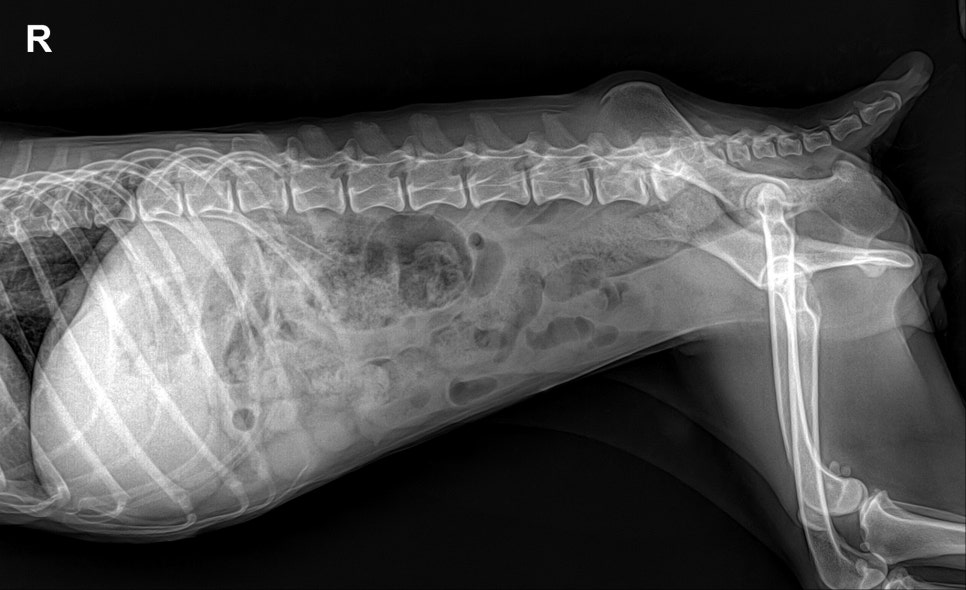

복부 방사선 검사: 이물 없음

- 복부 방사선 검사: 이물 없음